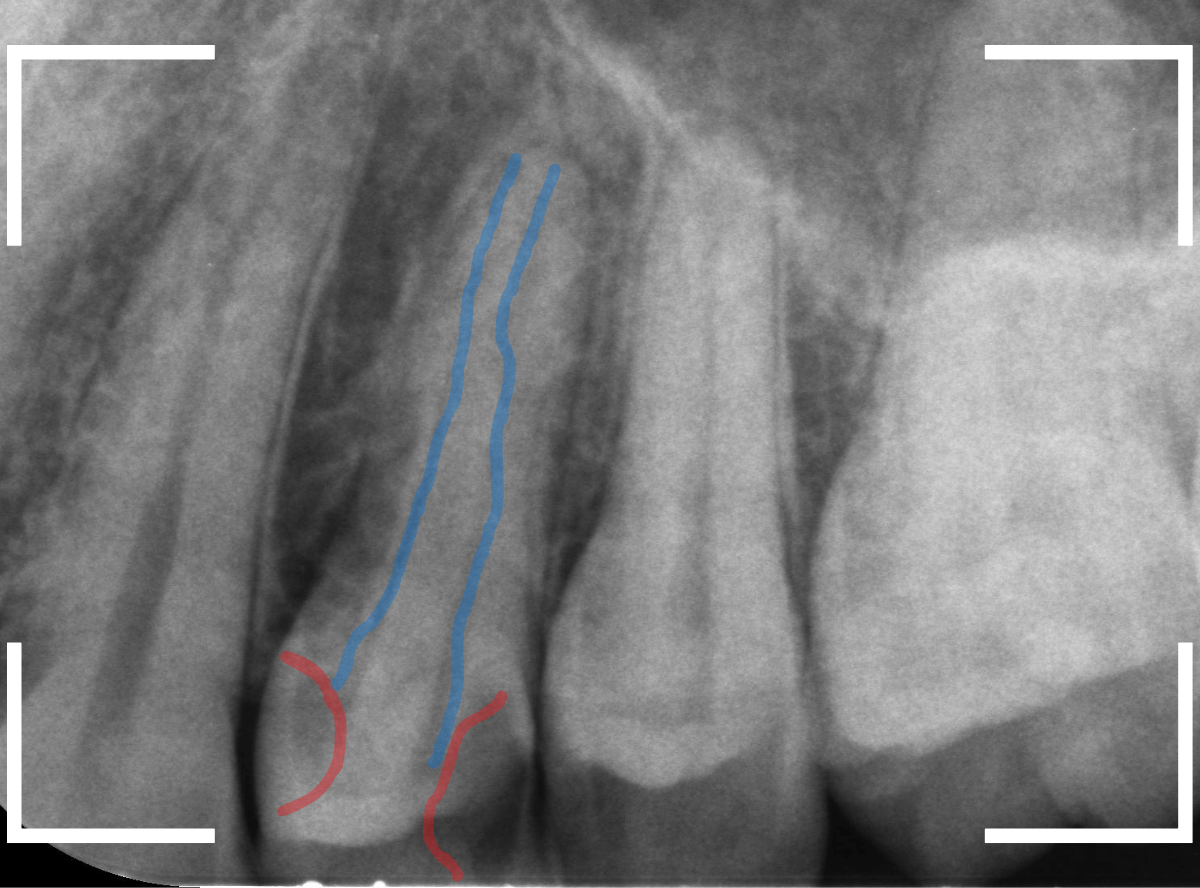

Case.21 神経に達しそうな2本の大きな虫歯

上の小臼歯の側面が明らかに虫歯になっている患者さんです。

患者さんは特に症状を感じてなさそうですが、恐らくは中で大きな虫歯になっているでしょう。

このように、自覚症状からだけでは虫歯の状況は診できません。

レントゲン写真で確認します。

青い線が歯の神経、赤い線が虫歯と思われる部分です。

2本とも、神経に達してしまいそうな大きな虫歯であると思われます。